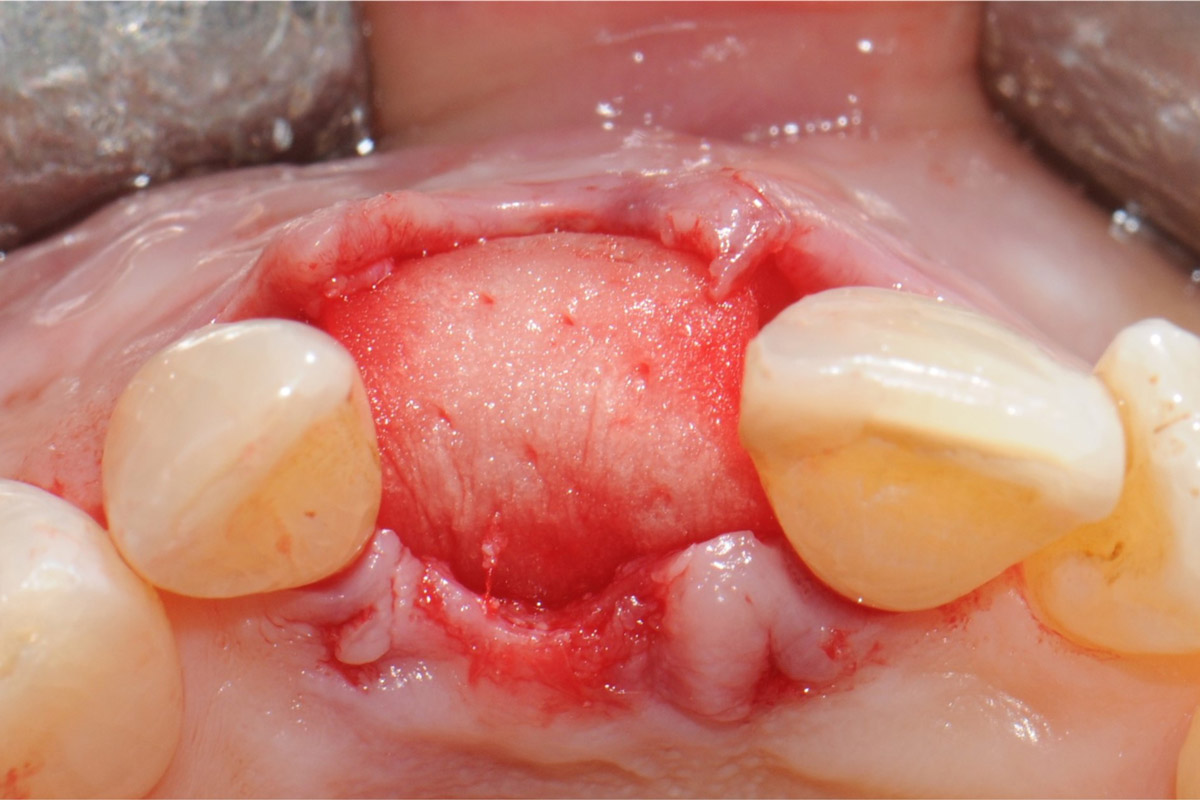

Intact socket following atraumatic tooth extraction